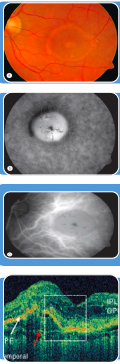

Atrophic AMD

Sign?

Atropic AMD

Greyish

Can’t really see where macula is

Can see edges of atrophy

If look clearly, can see blood vessels of choroid

Big scar over macula

Majority of rods and cones ( haemorrhage)

Progress slowly over time.

Jean below

yellowish, atrophic , drusen not obvious, vision affected severely

Window defect

Brightness of choroidal vessels

Ischaemic area - More profound appearance

Artifarct

RPE detachment